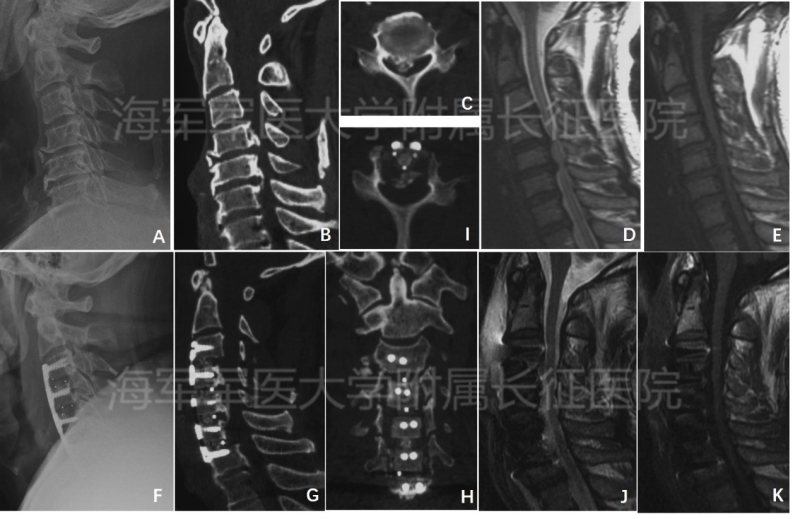

图3 前路椎体后纵韧带骨化复合体前移(ACAF)技术治疗颈椎OPLL合并硬膜囊骨化(A、术前颈椎X线片示颈椎后凸;B、C、术前颈椎CT平扫及三维重建提示合并硬膜囊骨化;D、E、术前MRI示脊髓受压;F、术后颈椎X线片;G、H、I、术后颈椎CT平扫及三维重建显示颈椎椎体、后纵韧带骨化以及硬膜囊骨化一同获得提拉前移;J、K、术后MRI示脊髓减压彻底,形态恢复良好)

对于合并硬膜囊骨化的颈椎后纵韧带骨化症患者,我们应用该技术进行治疗,避免了在后纵韧带骨化物和硬膜囊之间进行分离,从而完全消除了踏入 “陷阱”的机会,手术的安全性更高,同时将后纵韧带骨化物和硬膜囊骨化一同进行提拉前移,减压效果更可靠(图3)。